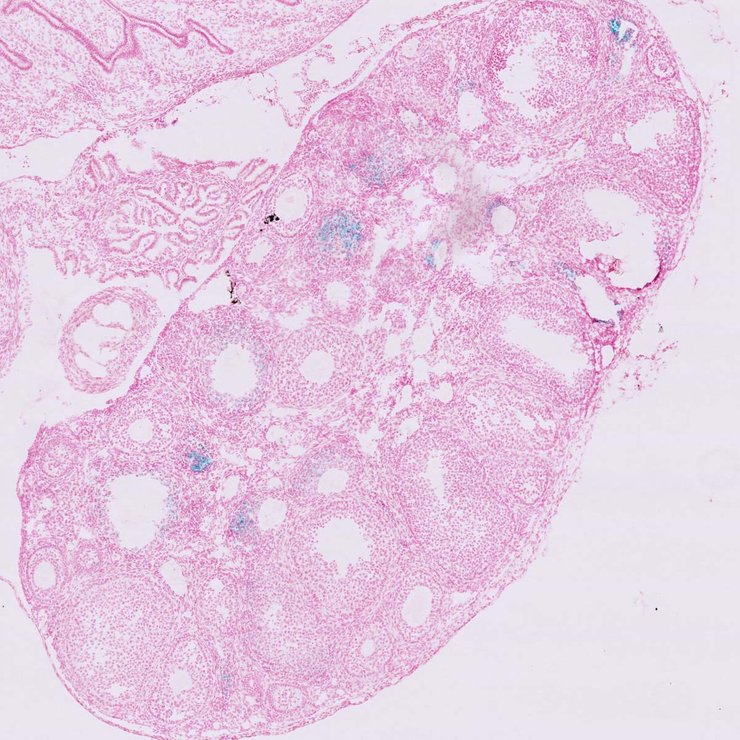

TS28: ovary Present JAX_1801483

TS28: thymus Present JAX_1801484